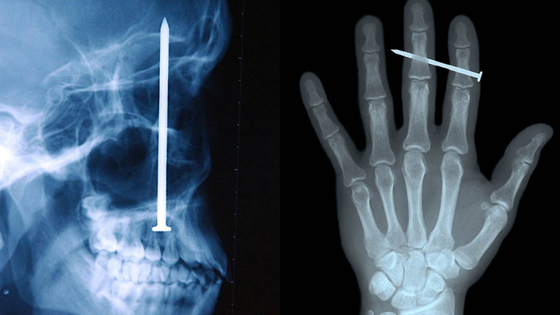

12 рентген‑фотографий, которые доказывают: идиотизм неистребим

Зачем и почему люди глотают разные странные вещи? Никто не знает точно, но медики утверждают, что таких “умников” гораздо больше, чем мы думаем.

Рентгенологи — люди с особо прокаченным чувством юмора. То, что они порой видят на снимках, у нормального человека вызовет настоящую истерику — а они только хмыкнут и отправят к хирургу. Что поделать, не расстраиваться же из-за каждого курьеза.

12 рентгеновских снимков: посмотрите, какими странными могут быть люди.